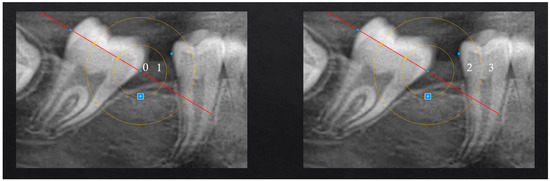

Spontaneous Second Molar Migration After MIH-Affected First Molars Extraction: A Radiographic-Based Method Evaluation

by Santo Andrea Stabilini, Lucia Giannini, Niccolò Cenzato, Francesca Olivi Mocenigo, Claudia Salerno, Cinzia Maspero and Maria Grazia Cagetti

Children 2025, 12(12), 1589; https://doi.org/10.3390/children12121589 - 23 Nov 2025

Background: Molar–incisor hypomineralization (MIH) represents a challenging dental condition, often requiring complex and invasive interventions. In severe cases, extraction of the first permanent molars (FPM) is frequently indicated. However, methods to assess the effectiveness of this approach in promoting spontaneous mesialization of the second permanent molars (SPM) through Orthopantomography (OPT), as well as the factors influencing this process, remain unexplored. Aim: This perspective study aimed to assess the effectiveness of novel radiograph-based methods for assessing spontaneous SPM mesialization after FPM extraction and to identify clinical and developmental factors associated with complete space closure. Methods: OPTs of 19 patients (12 males, 7 females; age range 6.2–13.8 years) who underwent extraction of 36 FPM due to severe MIH were analyzed by 2 operators. Pre- and post-extraction OPTs were evaluated using specifically developed geometric measurements of distances and angles to quantify SPM movement. Variables considered included patient age at extraction, dental developmental stage (Demirjian index), observation period, and presence or absence of the third permanent molar (TPM). The reliability of the proposed measurements evaluated through ICC (Intraclass Correlation Coefficient) resulted in values above 0.9, confirming excellent intra- and inter-operator reliability. Results: Complete or quite-complete mesialization (target scores 0–1 and ≤33% residual space) occurred in 78.6% of maxillary and 73.7% of mandibular sites. Maxillary SPMs showed more favorable spontaneous movement, exhibiting substantial uprighting (e.g., from −32° to 2°) and a higher frequency of complete or near-complete space closure (78.6% vs. 73.7% in the mandible). Developmental stages D–E of SPM were associated with successful outcomes. Conclusions: Early extraction of severely compromised first permanent molars (FPMs) can represent an effective treatment option to promote spontaneous mesialization of SPMs, particularly in the maxilla. The proposed radiograph-based measurement method demonstrated high consistency and reproducibility. Overall, this novel measurement approach may serve as a reliable and valuable tool for future clinical and research applications. Full article

Figure 1